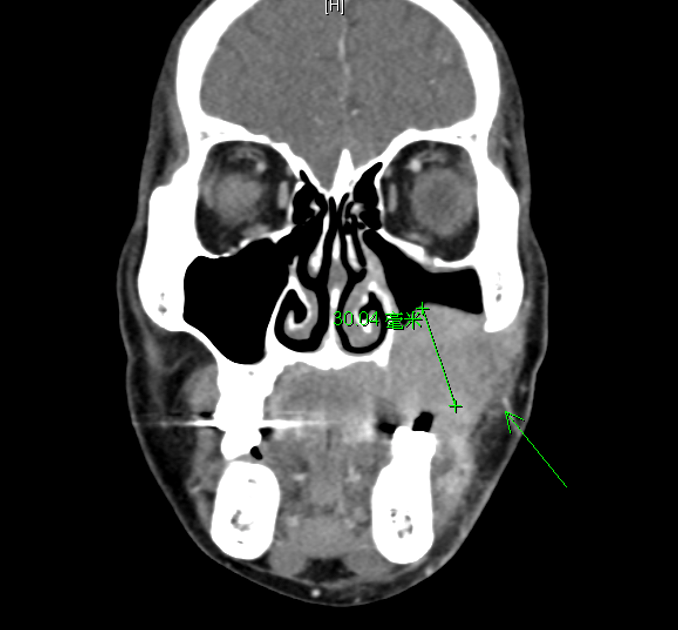

我們要討論的這位病患因為左臉頰腫塊合併牙關緊閉住院,一開始當作蜂窩性組織炎治療。電腦斷層顯示腫瘤已吃穿上頷竇,且有雙側頸部淋巴腫大,放射科一開始懷疑是頰黏膜癌,因此會診耳鼻喉科安排切片排除惡性腫瘤的可能性。第一次的切片結果顯示發炎細胞浸潤,沒有看到惡性腫瘤證據,病人又急著出院,因此就帶口服抗生素回家,在感染科門診追蹤。於門診追蹤時也發現有結合型高膽紅素血症,加上下腹部疼痛,建議再次住院。住院後腹部電腦斷層發現有腹膜炎,及乙狀結腸腫大,疑似腸炎。入院後繼續抗生素治療,並針對高膽紅素血症會診肝膽腸胃科,追蹤免疫學檢查,發現ASMA陽性,然而由於病患拒絕肝臟切片檢查,因此沒有進一步確認免疫性肝炎。後來再次會診耳鼻喉科安排切片,病理報告一樣是沒有惡性發現,病患也再次要求口服抗生素出院。

出院後約1-2個禮拜,病患因右上腹痛再度來急診,第三次住院由簡榮南副院長primary care。電腦斷層顯示腹膜炎(尤其是右上腹)、雙側肋膜積液及膽囊壁增厚。病患住院期間再次接收左臉頰切片,但結果仍是沒有發現惡性腫瘤。簡副認為,一個這麼大的腫瘤,連續多次切片都沒有發現是惡性,那應該要往其他方向去思考。因此在查閱過相關資料後,當科PGY學妹許昕瑜醫師抽了IgG、IgG4及檢驗可能造成頭頸部腫大的病毒、黴菌感染(包含EBV, aspergillus等),結果意外發現IgG、IgG4 上升,也因此懷疑到IgG4 related disease。會診風濕免疫科時,當時根據放射科報告,認為有骨頭侵犯等較惡性的表現,比較不像IgG4 related disease。然而最後還是有請病理科染IgG, IgG4, 也發現有符合IgG4 related disease的病理診斷,包含淋巴球及漿細胞浸潤合併纖維化,IgG4:IgG陽性細胞比>40%及IgG4陽性細胞> 10/HPF。同時,病患合併一個以上器官的腫大或腫塊,以及血清IgG4>135mg/dL,藉此確診IgG4 related disease,也給予病患臉頰腫、腹痛(IgG4相關性自體免疫肝炎、膽管炎及腹膜炎)及肋膜積水一個合理的解釋。病患也開始接受類固醇治療,牙關緊閉及左臉腫的症狀也在治療後明顯改善,肝功能的各項指數也逐漸恢復正常。